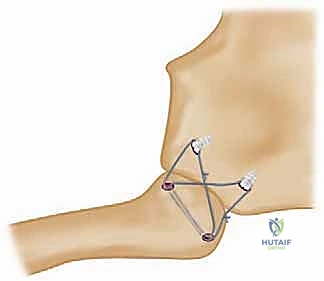

لا يمكن ببساطة خياطة الأربطة الممزقة لضمان الاستقرار. لذلك، يستخدم الدكتور هطيف تقنية متقدمة لإعادة البناء باستخدام "رقعة وترية" (Tendon Graft).

* حفر الأنفاق العظمية: يتم حفر ثقوب دقيقة جداً في عظم الترقوة وعظم القص باستخدام أدوات جراحية متطورة.

5. تمرير الرقعة وتثبيتها (تقنية الرقم 8)

يتم تمرير الرقعة الوترية عبر الثقوب العظمية بنمط يشبه الرقم 8 (Figure-of-eight). هذه التقنية الميكانيكية الحيوية توفر قوة استقرار هائلة تحاكي قوة الأربطة الطبيعية (الرباط الكبسولي والرباط الضلعي الترقوي).